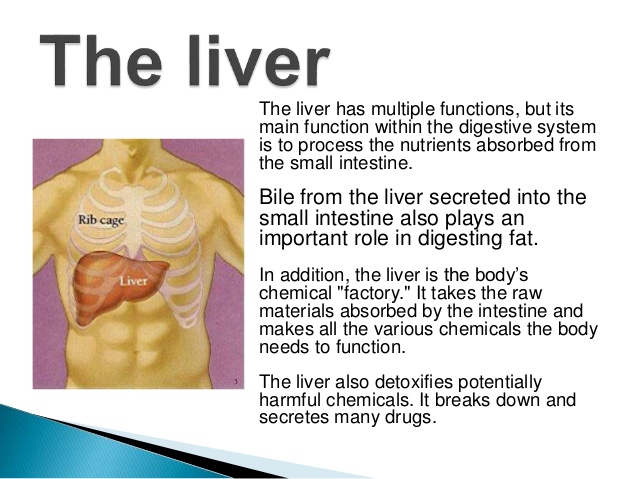

4. The digestive system (human)

- Parts of the digestive system from mouth to anus.

- Digestion at various points - mouth, stomach, intestine.

- Enzymes as catalysts that aid digestion (digestive juice)

- End products of digestion

- Absorption and storage of food.